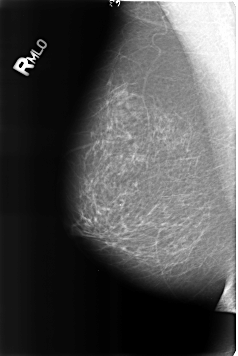

Digital Database for Screening Mammography

Volume: benign_01 Case: B-3159-1

B_3159_1.RIGHT_MLO

RIGHT_MLO LINES 4616 PIXELS_PER_LINE 3088 BITS_PER_PIXEL 12 RESOLUTION 50 NON_OVERLAY

FILE: B_3159_1.LEFT_MLO.OVERLAY

TOTAL_ABNORMALITIES 1

ABNORMALITY 1

LESION_TYPE CALCIFICATION TYPE LUCENT_CENTERED DISTRIBUTION N/A

ASSESSMENT 2

SUBTLETY 5

PATHOLOGY BENIGN